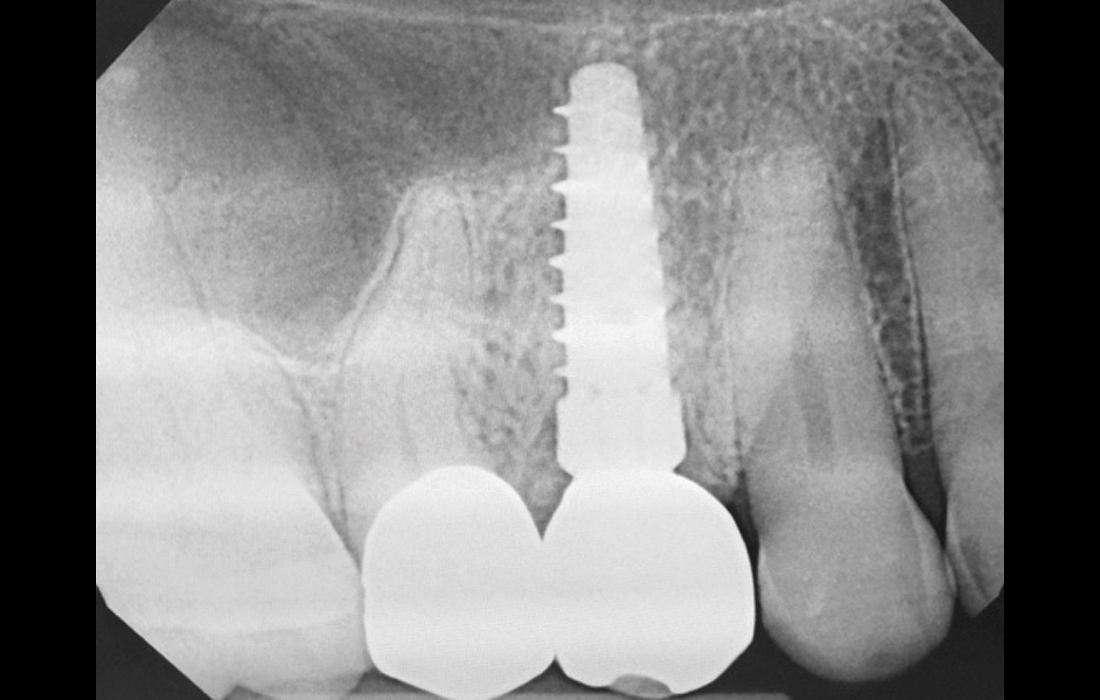

Steri-Oss Implant CSM Image 1 V15I2

This longstanding patient (left) of more than three decades has had various implants placed over the years, including a Steri-Oss implant Dr. Hahn designed with a machined collar. Follow-up radiographs have consistently shown excellent crestal bone preservation around the machined collar of the implants placed in the maxilla, and the Steri-Oss implants have been functioning for nearly 35 years. Note the ample volume of bone above the platform of a Hahn Tapered Implant placed in the posterior (right).